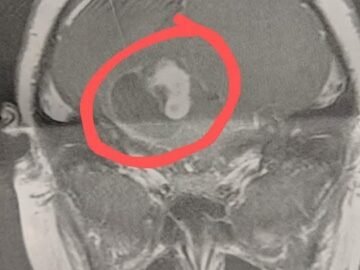

In December 2020, I took my 9-year-old son for his yearly physical. It was supposed to be quick — maybe 45 minutes at most. He...